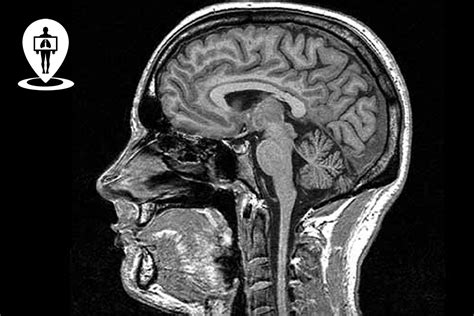

Le tecniche di imaging come la Tomografia Assiale Computerizzata (TAC) e la Risonanza Magnetica (MRI) offrono immagini dettagliate del cervello e del midollo spinale, permettendo di identificare malformazioni, lesioni o altre alterazioni strutturali. La Risonanza Magnetica Angiografica (MRA) visualizza i vasi sanguigni cerebrali, mentre la Risonanza Magnetica Spettroscopica (MRS) fornisce informazioni sul metabolismo cerebrale.